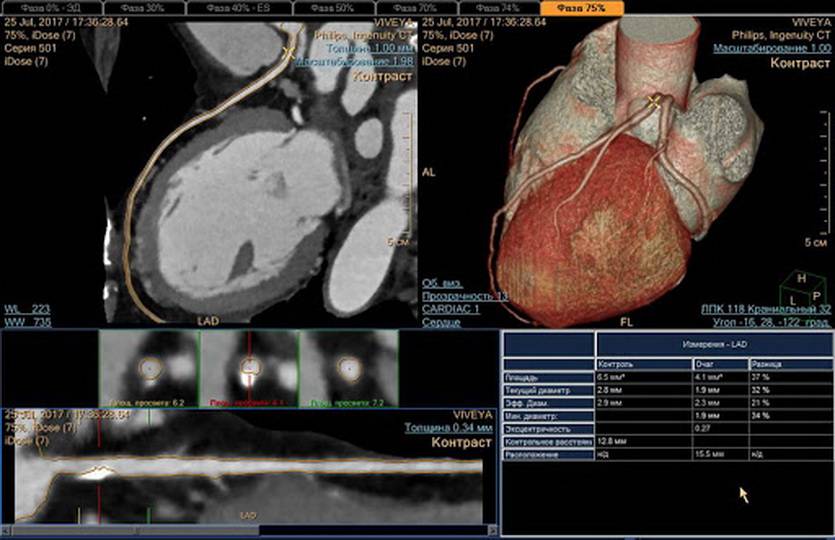

а – обычный снимок грудной клетки, б – компьютерная томография

При одинаковом физическом принципе построения изображений при рентгене и КТ органов грудной клетки различны траектория прохождения рентгеновских лучей через область интереса и техника визуализации. Указанное влияет на информативность изображений.

Компьютерная томография – усовершенствованное рентгеновское исследование. Современные мультиспиральные сканеры способны выполнить несколько десятков снимков в разных проекциях за одну задержку дыхания. Дополнительные программы автоматической корректировки экспозиции помогают уменьшить лучевую нагрузку в 1,5-2 раза. При необходимости доступны мультипланарные реконструкции изучаемой зоны, оценка сосудов с использованием ангиорежимов, изучение патологии с любого ракурса.